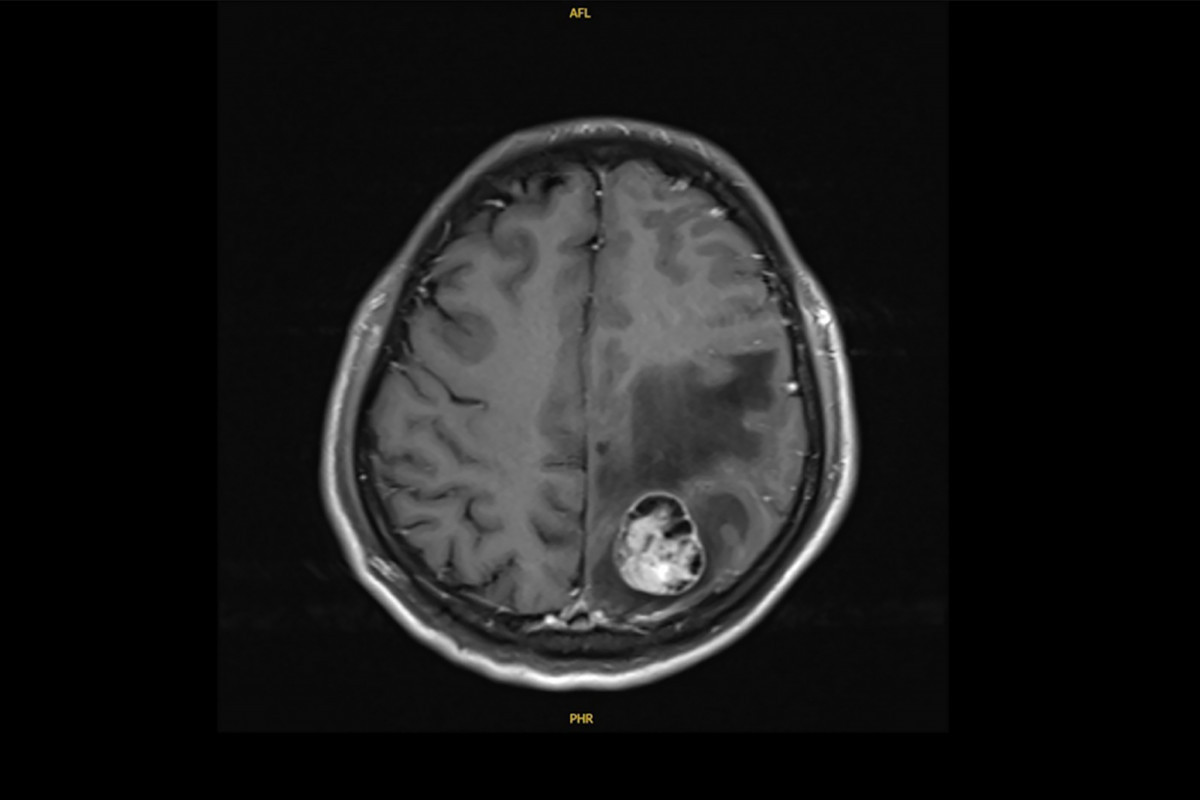

41歲的許先生原為文具業務,是家中主要經濟支柱。三年前某日清晨,他突然右側肢體無力、抽搐倒地,家人緊急送醫。經電腦斷層與核磁共振檢查,發現腦部有3公分腫瘤,右下肺另有4公分腫塊,確診為肺腺癌合併腦轉移。

許先生的腦部核磁共振檢查發現腫瘤達3.1公分,進一步確診為肺腺癌轉移。圖/彰基醫院提供